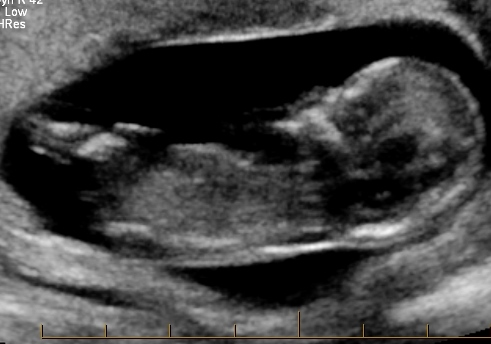

I would lean boy as we'll

I think boy too x

All boy